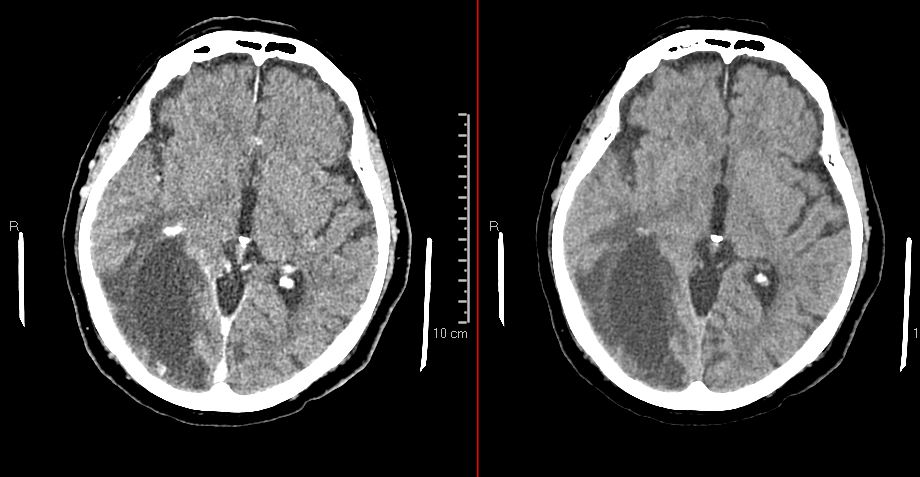

CT Scan.JPG